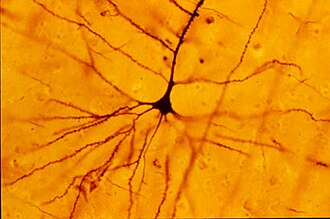

Specimens